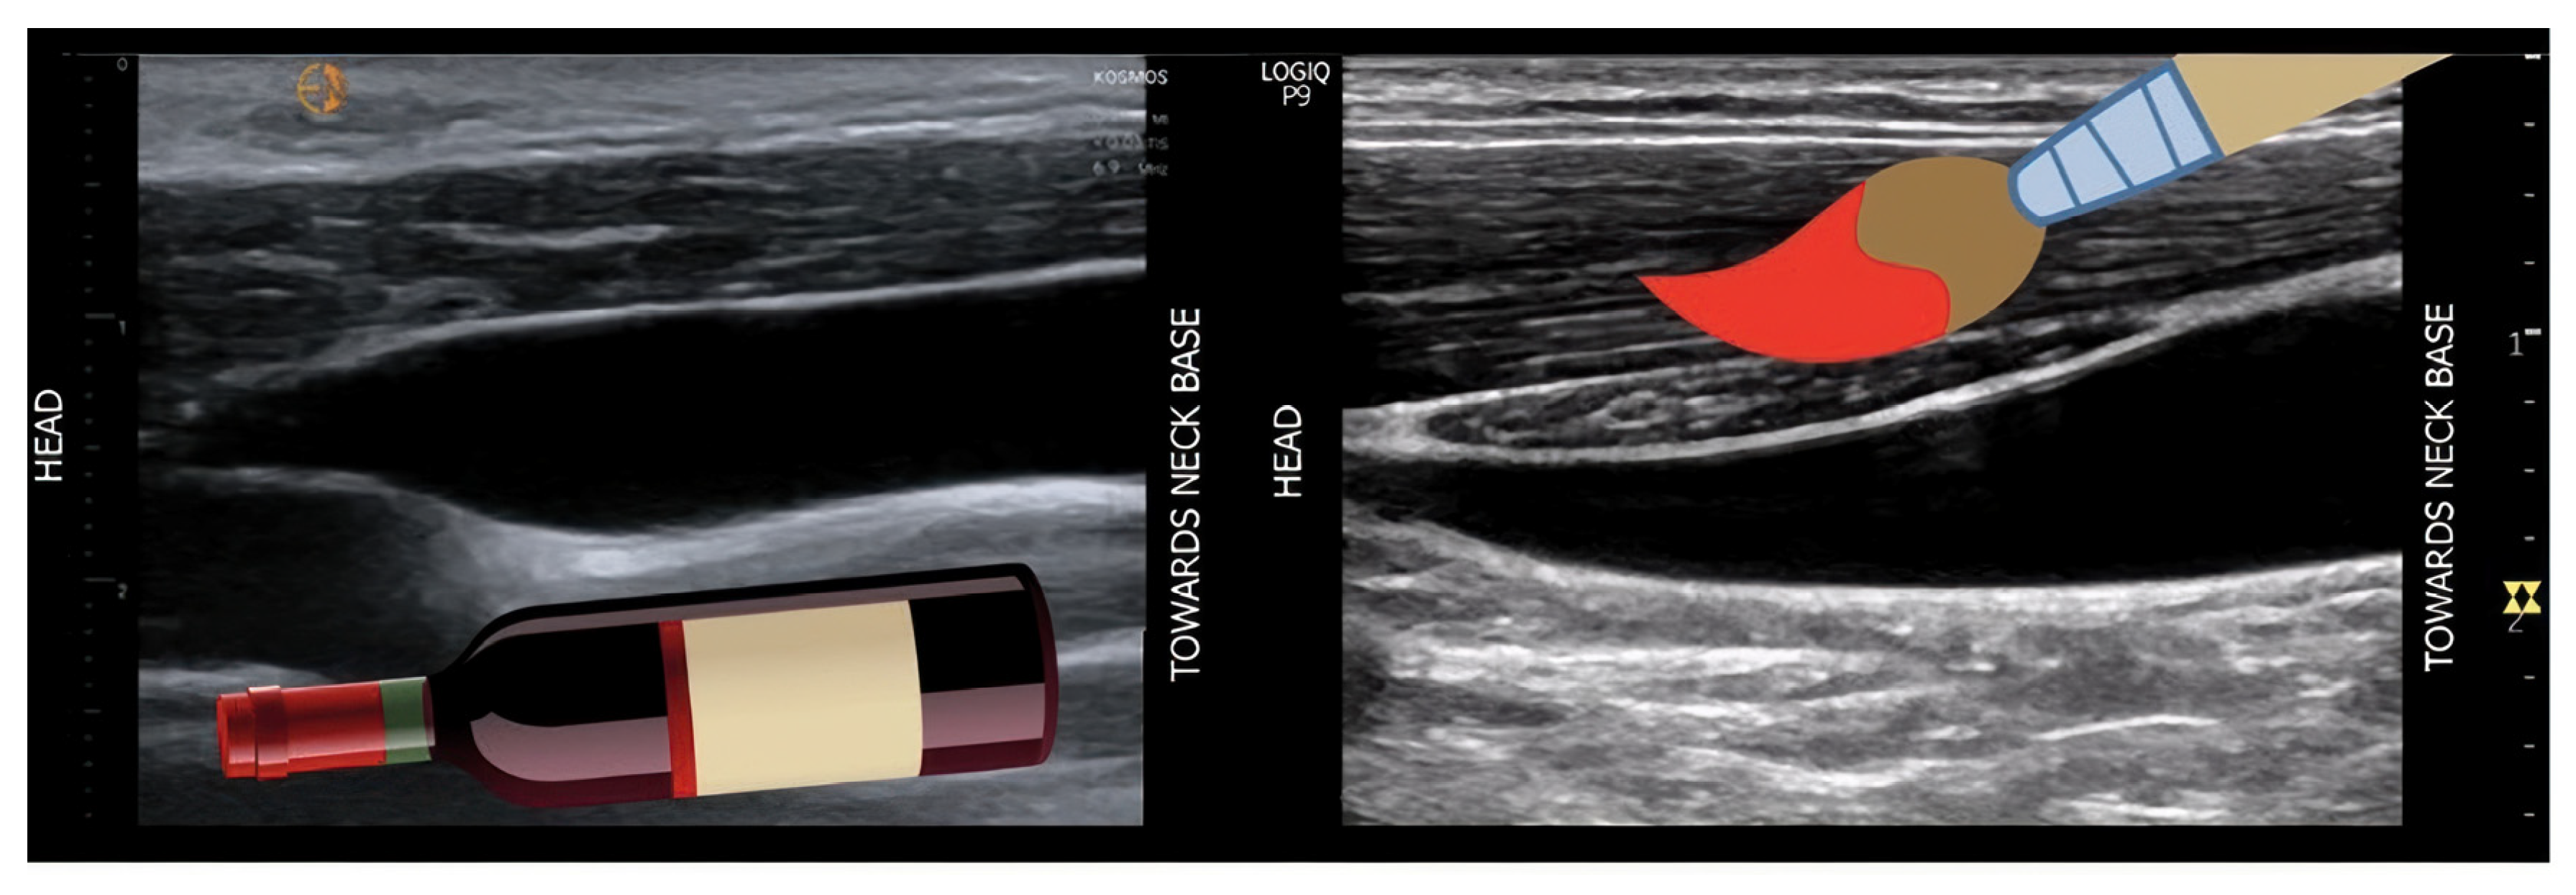

B-Mode Renal Ultrasound and Renal Artery